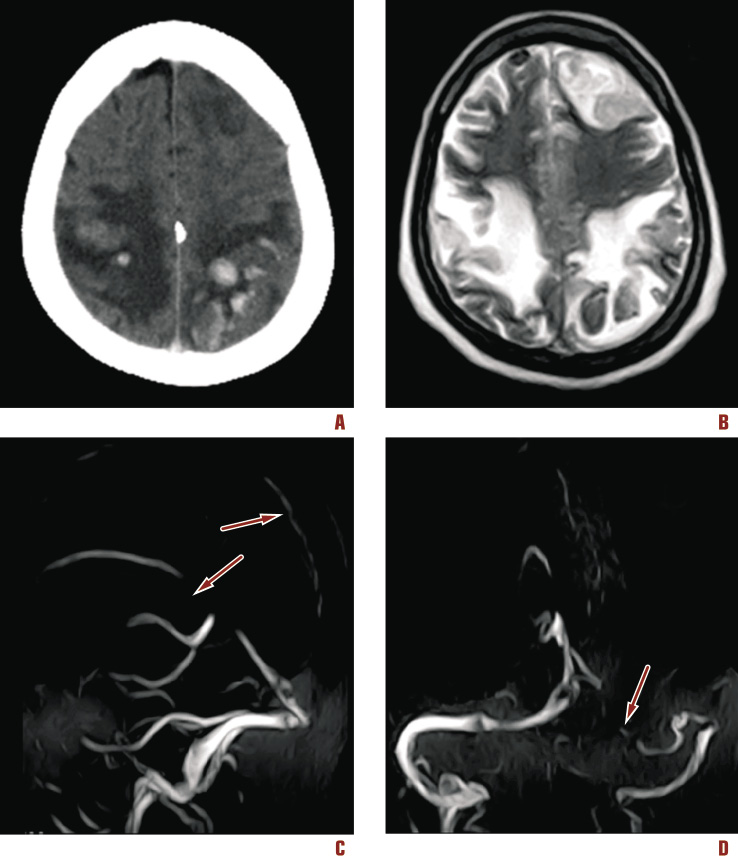

An unenhanced computed tomography (CT) scan in sagittal view showed spontaneously hyperintense superior longitudinal sinus, and bilateral occipital hemorrhagic infarctions. MRI showed hemorrhagic infarctions and occlusion of several sinuses. (Figure 1). Electroencephalogram showed non-convulsive status epilepticus.

Figure 1. Neuroimaging at admission. (A) CT scan shows bilateral occipito-parietal infarctions with hemorrhagic transformation and peri-lesional edema; (B) MRI in Axial T2-weighted image shows increased signal intensity in both occipital and left frontal lobes; (C) MRI venography demonstrating occlusion of superior and inferior sagittal (arrows) and (D) left transverse sinus (arrow)

After the diagnostic imaging, the patient was transferred to the neurointensive care unit. She was sedated (midazolam 3-5 mg/kg/h), anesthetized (remifentanil 0.25-0.4 mcg/kg/min) and mechanically ventilated. Then she was treated with physiologic neuroprotection [5]5 and osmotherapy. At the same time an anticoagulation therapy with low weight molecular heparin (enoxaparin 1 mg/kg twice daily) and warfarin (5 mg/day) was started in order to obtain a targeted international normalized ratio (INR) of 2.5-3.